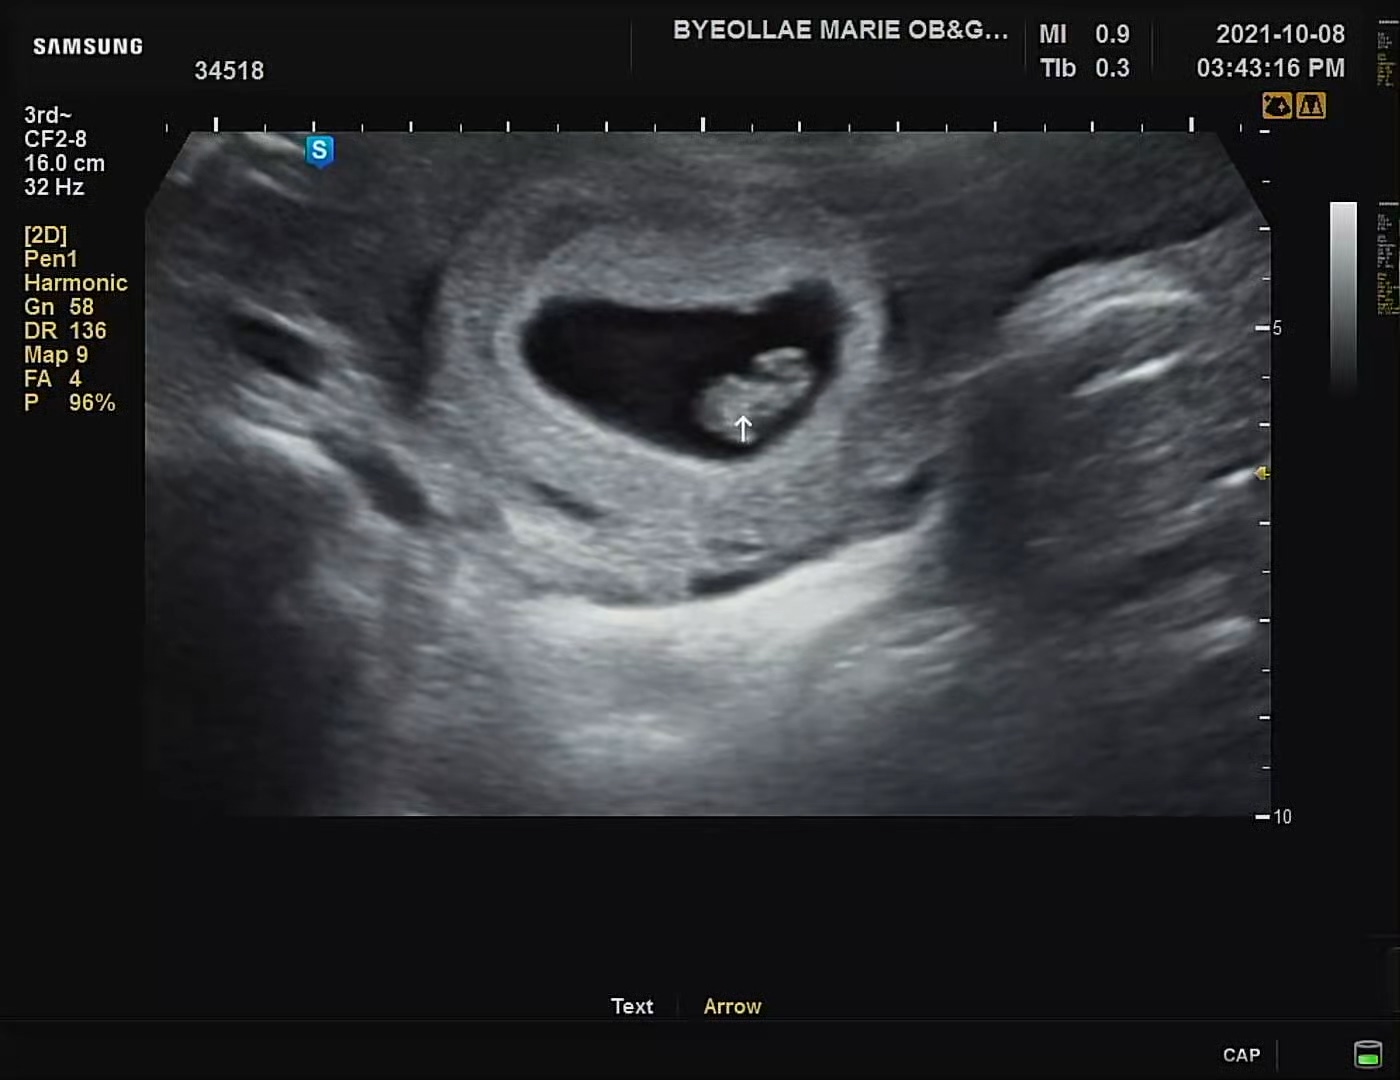

아내도 피고임이나 특이사항 없이 컨디션이 좋다고 하였다. 이 시기의 아기는 뇌의 신경이나 눈 및 귀의 신경이 급속히 발달한다고 한다. 또한 이때는 난황낭이라는 작은 주머니로 영양을 공급받는데, 그것에 대한 설명도 해주셨다.

얼핏 초음파의 실루엣으로 보았을 때 다리를 오므리고 있는 모습이 있는 것 같기도 하고..기분탓인가..